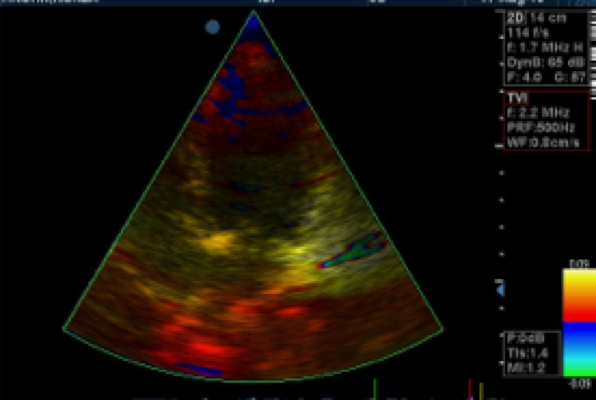

Gewebedoppler

In diesem speziellen Verfahren können Bewegungen der Herzwände, Herzmuskelversteifungen, oder ein Elastizitätsverlust des Herzmuskels während der Füllphase der Herzkammern festgestellt werden.